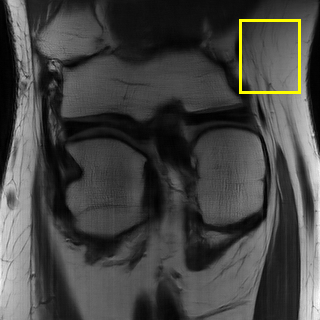

We also provide visual comparisons in Fig. 7- 9. According to these images, we can see that EAMRI has fewer bright dots in the heatmaps and more clearer and accurate edges in the zoomed-in areas. The above quantitative and qualitative analysis fully demonstrate the effectiveness of the proposed EAMRI. Due to the page limit, more visual comparisons can be found at https://github.com/MIVRC/EAMRI.

(a)

(b)

(c)

(d)

(e)

(f)

(g)